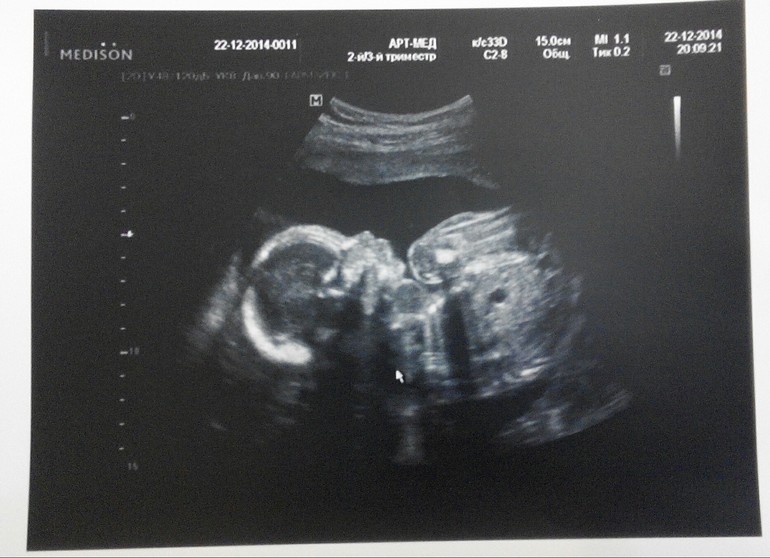

Фото с УЗИ:

СкринингИтак, срок по ПДМ 22 нед и 2 дня, результаты УЗИ:

Предлежание: тазовое

Бипариетальный размер головы: 51 мм

Длина бедренной кости: лев 36, прав 36

Длина плечевой кости: лев 36, прав 36

Окр головы: 190 мм

Окр живота: 164 мм

Масса: 420 гр

ЧСС: 156 уд/мин

Размеры плода соответствуют 21 нед и 3 дн.

То есть отставание от срока по месячным - неделя. Поэтому ПДР передвинули на 01.05.2015 вместо 25.04.2015.

Внутри все на месте и без паталогий :-)

И да, это все таки девочка :-) на мальчика будем стараться в след раз ))